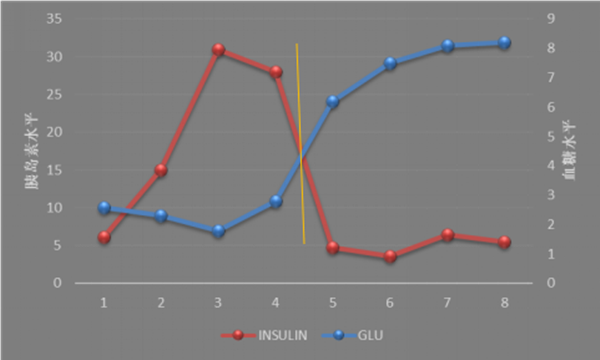

患者与家属因既往脑膜瘤手术史,对于传统外科手术心存畏惧,经过多方权衡讨论后,家属决定转入我院接受超声胃镜引导下细针胰腺穿刺及肿瘤消融治疗。入院后,在全体内分泌科医护人员,尤其是荆爱玉教授、焦杨主治医师、郑乐护士治疗小组的周密工作下完善相关检查,维持血糖浓度。经消化内科王进海主任及内分泌科徐静主任协调,于2016年12月23日上午9时,由消化内科马师洋与史海涛主治医师操作,内镜室李雪荣护士长精心配合,于超声胃镜引导下行胰腺占位穿刺活检,并行无水乙醇消融治疗术。手术操作顺利完成,全程约半小时,术中患者无特殊不适,术后感轻微上腹不适,血糖水平逐渐恢复正常,当日晚7时左右患者上腹部不适消失,停用静脉补充葡萄糖液后,血糖依然维持在6-8mmol/L。术后观察4日,患者未再出现低血糖。

术后恢复良好:血糖保持正常平稳,胰岛素水平恢复正常